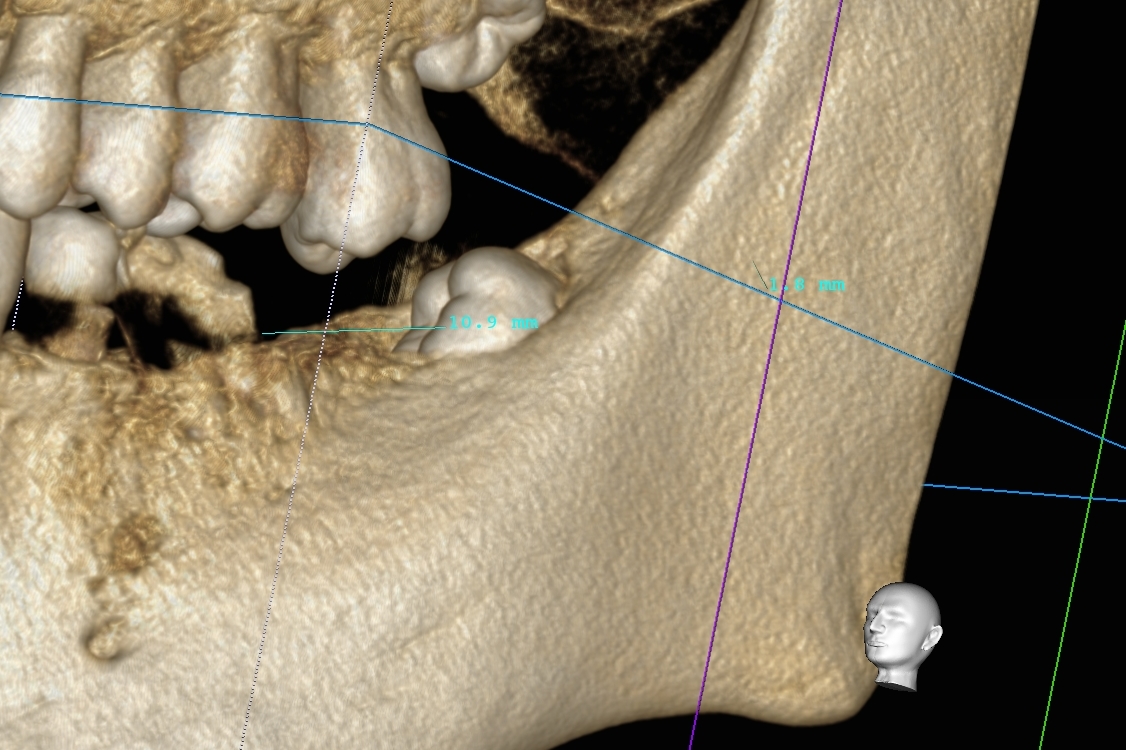

阪急池田駅 アールデンタルクリニックです。入れ歯の悩みの1つ、外れてしまう・・・。そんな悩みを解消する方法の1つに、オーバーデンチャーが存在します。簡単に説明すると、マグネットのようなもので入れ歯を固定するのです。固定する歯がなければ少数のインプラントを使用することになりますが、治療前後で生活が一変します。具体的に、入れ歯が外れなくなった、硬いものが今までより食べれるようになった、大きかった入れ歯が小さくなり会話がしやすくなった、などなど。実際に来院していただくと、模型を用いて実際にどのようなものか体感して頂けます。ぜひ一度、ご興味のある方はご相談下さい。